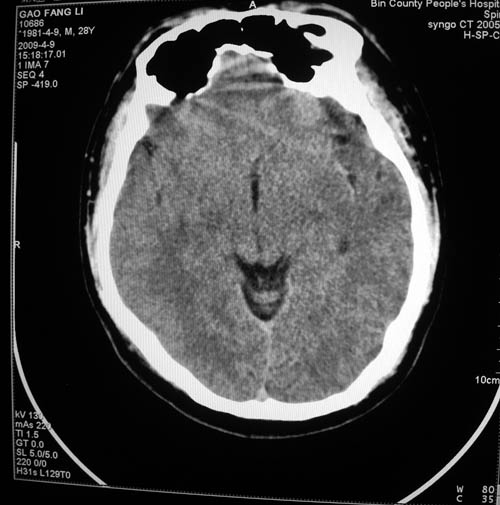

标题: CT19297:男,28岁,头痛待查。

男,28岁,头外伤来就诊。左侧基底节区是腔梗吗?

考虑脉络膜裂囊肿

我看还是豆状核上腔梗

考虑脉络膜裂囊肿的可能性大。

考虑左侧脉络膜裂囊肿。